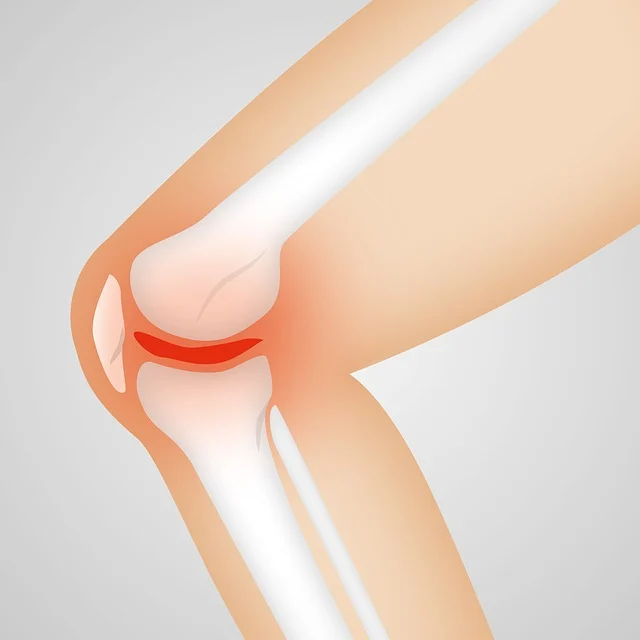

- 연골의 지속적인 마모: 연골연화증이 진행되면, 슬개골과 대퇴골 사이의 연골이 계속해서 마모될 수 있습니다. 이는 연골이 점차 얇아지고 손상되면서, 뼈와 뼈가 직접 마찰하는 상황으로 이어질 수 있습니다.

- 관절염 발전: 연골연화증은 골관절염을 비롯한 다른 유형의 관절염으로 발전할 위험이 있습니다. 연골의 지속적인 마모와 염증은 관절의 영구적인 손상을 초래할 수 있습니다.